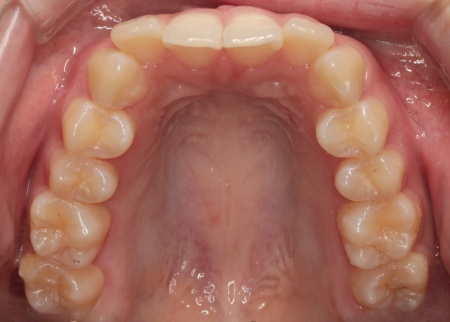

20代女性 乱れた上下の歯並びをハイブリッド矯正で改善した症例

「歯並びが気になるので治療をしたい」とご相談いただきました。

拝見したところ、上下の歯はデコボコに生えている状態でした。

このままでは見た目が気になるだけでなく、磨き残しが起こりやすくなることで虫歯や歯周病などの発症リスクが高まります。

以上のことから、歯並びを改善する矯正治療が必要だと診断しました。